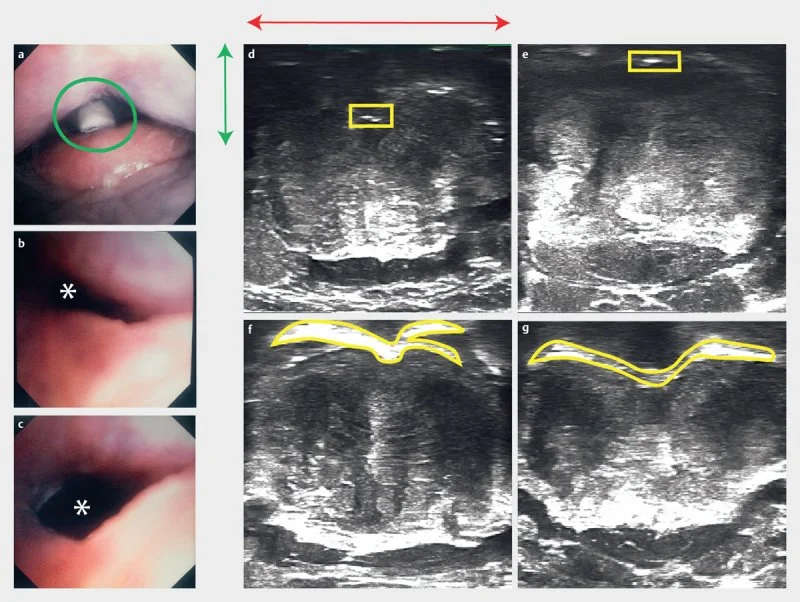

Confirming that ultrasound can detect airway collapse: These images validate the use of ultrasound to measure airway obstruction by comparing what an endoscope sees inside the airway with what an ultrasound detects from outside the neck. Panel A shows a photograph of the base of tongue and epiglottis, with the tracheostomy tube (green circle) used to create controlled airway collapse by applying suction. Panels B and C show the airway through an endoscope before and after releasing suction — collapsed in B, open in C. The asterisk marks the airway lumen. Panels D and E show the corresponding ultrasound images from outside the neck during suction. The yellow boxes highlight a compressed, faint air-tissue boundary — the ultrasound signature of a collapsed airway. The green and red lines in panel D confirm this interface sits in the posterior 40% of the neck. Panels F and G show the air-tissue interface manually outlined in yellow, corresponding to the open airway in panel C. Across all panels, the ultrasound signal faithfully tracks the real state of the airway — collapsing and reopening in step with what the endoscope directly confirms.